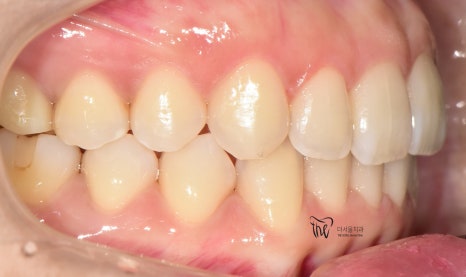

구강 내 사진을 먼저 보여드리면, 윗니가

아랫니를 깊게 물고 있어서 아랫니가 거의

눈에 띄지 않는 것을 보실 수 있습니다.

딱, 전형적 과개교합 의 양상을 보여주고 있습니다.

그러면서 치아의 중심선이 맞지 않으면서

악궁의 크기 또한 비대칭인것을 볼 수 있네요.